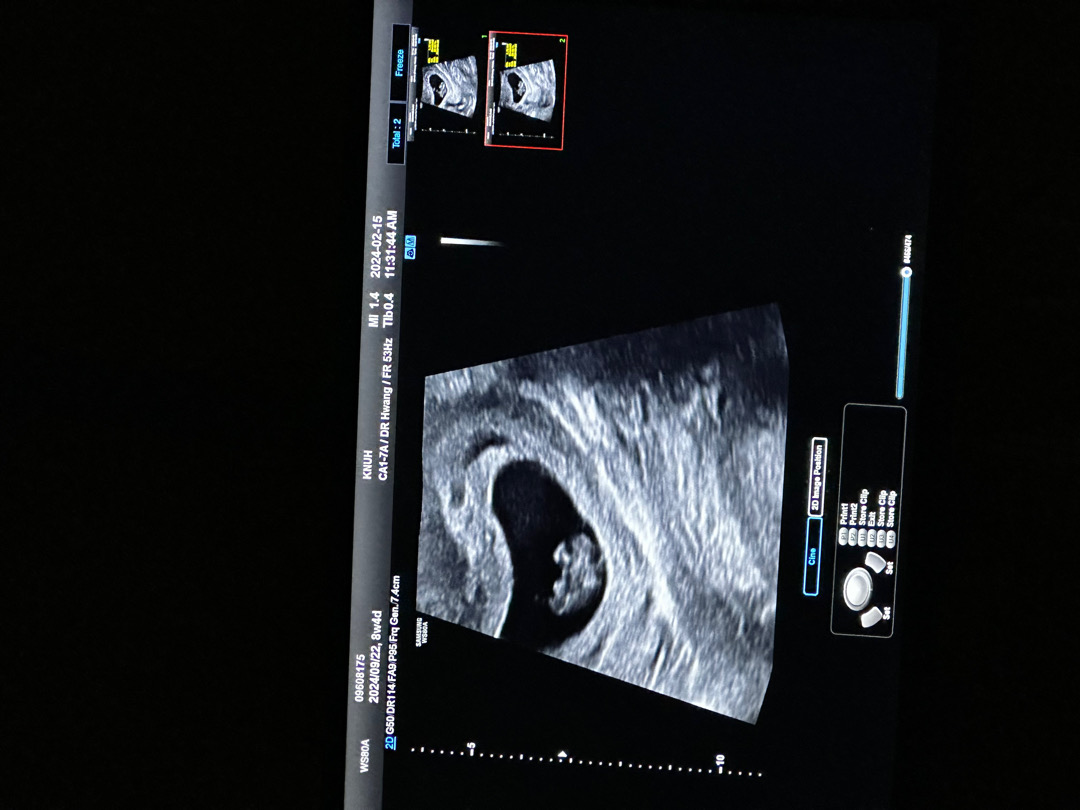

8주4일!

다른분들은 예쁜 젤리곰인데 우리애기 ㅋㅋㅋㅋㅋㅋㅋ무슨 모양인지 모르겠어요,,,